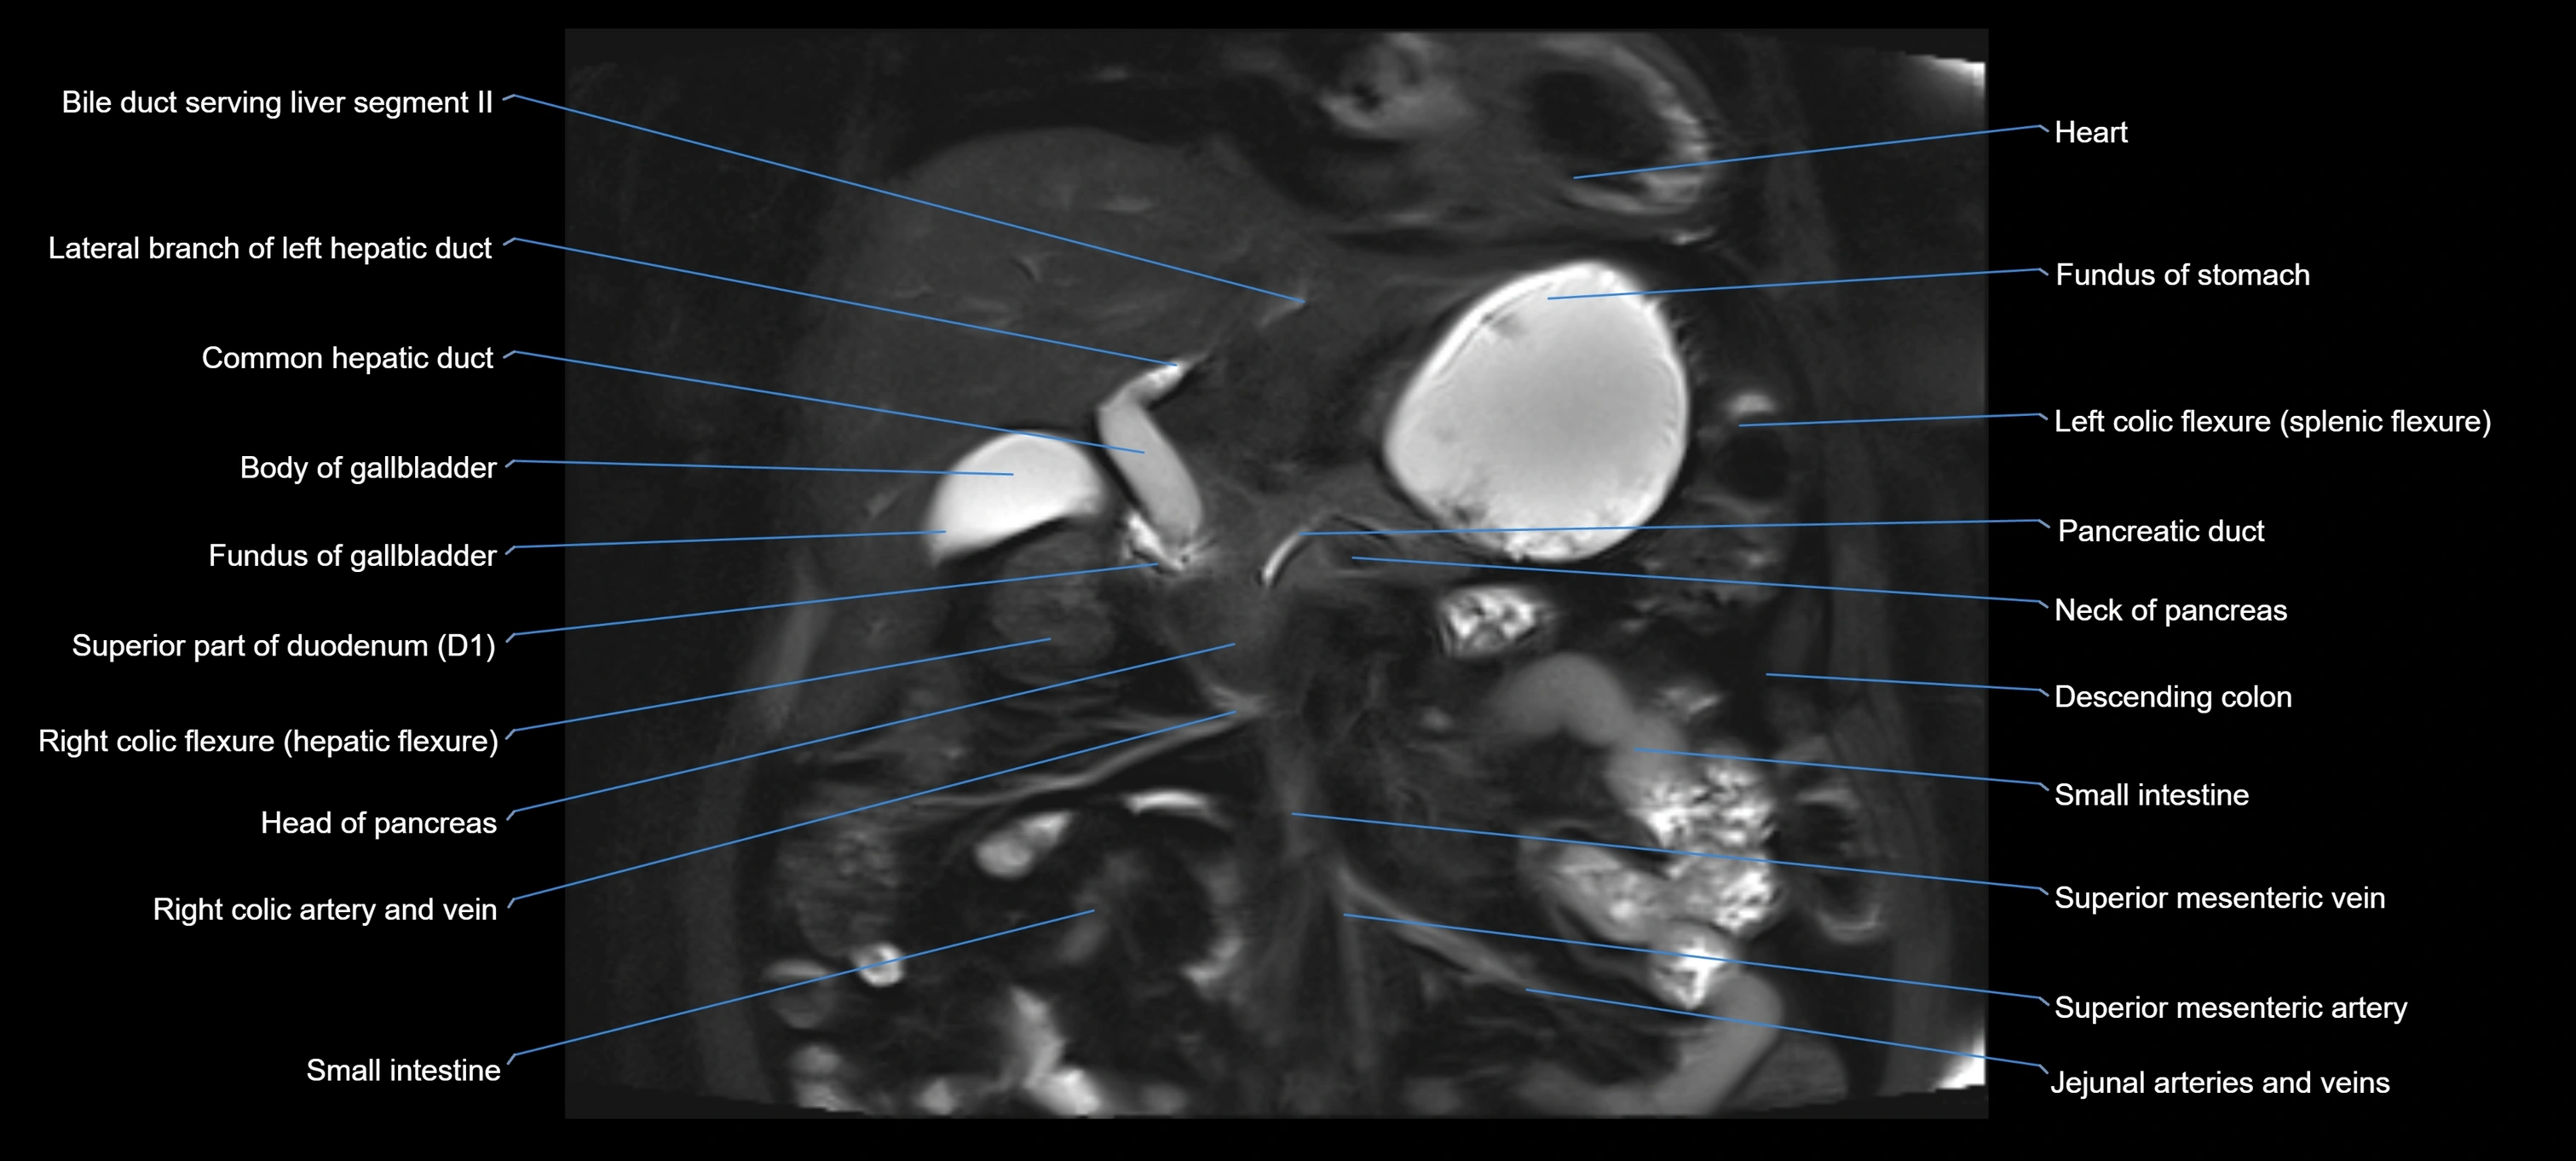

MRI image

image